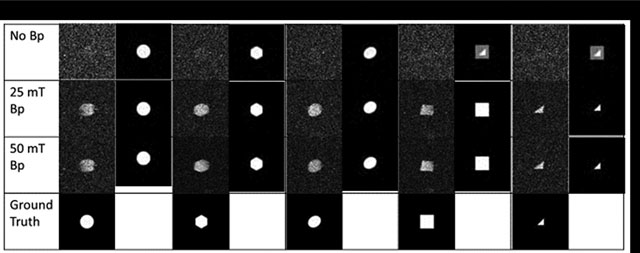

We illustrate how some of these risks arise in machine learning for medical images. For example, in facial recognition, the image to be recognized is already in the machine learning database. A noisy low-resolution picture just needs to be matched with the library’s ground truth images. But in medical image analysis, each patient can present new one-off structures which are not present in the existing database. This enables algorithms to hallucinate structures that are not actually present as the machine learning attempts to bring information from its library of data to enhance the current image. Consider this simple imaging experiment performed in our laboratory on a 4 mili-tesla low field MRI system described in [25]. We constructed simple geometric phantoms as seen in Figure 1. We trained a deep learning network on a library of ideal perfect geometrical shapes without noise representing the phantom shapes (squares, triangles, circles) as described in [10]. By varying the field strength of an additional (prepolarizing field) between 0 tesla (off), 25 mili-tesla, and 50 mili-tesla we produced images with increasing improvement in signal-to-noise. Notice that when the prepolarizing field was turned off, there is maximal noise in the raw images. At higher prepolarizing field, the deep learning network is able to reproduce the correct image. But when the signal-to-noise is low (the prepolarizing field is off), the deep learning network overlays the shapes in its library and produces an image that could exist, but in fact, does not. It hallucinates when bringing the library information to handle noisy and uncertain parts of the images.

Figure 1:

The results of an imaging experiment on a prepolarized low field MRI with a 4.23 mT readout field. Five geometrical phantoms with cross sections of a circle, hexagon, oval, square, and triangle, were constructed and filled with water. Images were collected with the prepolarized field (Bp) off, at 25 mT, and 50 mT. Ground truth was synthetically generated using a computer. A deep learning library was trained with artificially degraded images at the SNR levels calculated from the experimental images. Enhanced images are displayed in each column next to the experimental images for comparison. Note the production of hallucinations in the images at upper right.